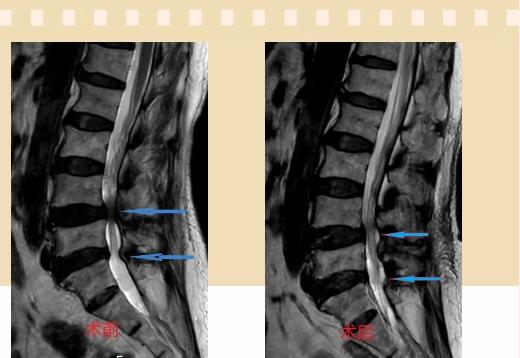

入院后李鵬副主任醫(yī)師為其進(jìn)行了詳細(xì)的查體,完善了術(shù)前的檢查,明確診斷為:腰椎管狹窄癥(L4/5、L5/S1),病人合并2型糖尿病,請(qǐng)內(nèi)分泌科會(huì)診,穩(wěn)定血糖后,麻醉科會(huì)診病人,排除手術(shù)禁忌,李鵬為病人制定了手術(shù)方案:?jiǎn)蝹?cè)入路雙側(cè)減壓(ULBD)。

手術(shù)采用三個(gè)微創(chuàng)小切口,兩個(gè)節(jié)段減壓手術(shù)時(shí)間2.5小時(shí),出血50ml。術(shù)后2天腰圍保護(hù)下床活動(dòng),術(shù)后5天順利出院。

傳統(tǒng)腰椎管狹窄癥的手術(shù)治療,往往需要切開(kāi)減壓,同時(shí)需要內(nèi)固定融合術(shù),創(chuàng)傷很大,同時(shí)可能需要輸血,臥床時(shí)間較長(zhǎng),病人合并糖尿病,感染風(fēng)險(xiǎn)也高,而本次采用的UBE-ULBD手術(shù)切口更?。悠饋?lái)約3cm,如果是單節(jié)段狹窄只需要不到2cm切口)、創(chuàng)傷更小,術(shù)后恢復(fù)較快,可以更早地恢復(fù)正常活動(dòng)。

此外,手術(shù)保留了病變節(jié)段的穩(wěn)定性,是一種微創(chuàng)的椎管減壓手術(shù),能通過(guò)切除部分椎板、關(guān)節(jié)突關(guān)節(jié)、黃韌帶來(lái)解除神經(jīng)根和硬膜囊的壓迫,不需要額外行腰椎內(nèi)固定術(shù),不需要螺釘及融合器的植入,病人術(shù)后腰椎的活動(dòng)度不受影響。(盧   闖  劉   旭   袁錦鈺)